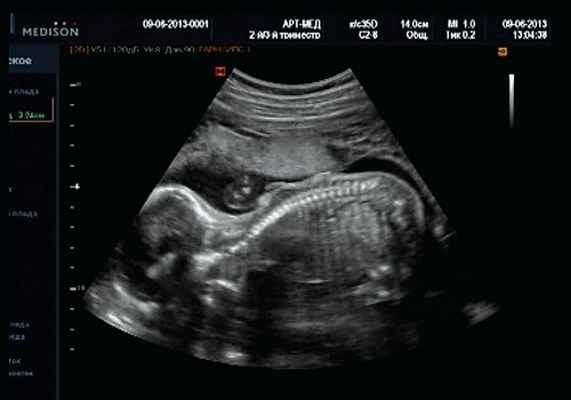

Клиническое наблюдение 3

Беременная 27 лет, обратилась в клинику в 18 нед. При эхографии обнаружен синдром Арнольда - Киари II, умеренно выраженная гидроцефалия (рис. 17).

Рис. 17. Беременность 18 нед. Гидроцефалия.

В крестцовом отделе позвоночника выявлена spina bifida cysticа (рис. 18).

Рис. 18. Беременность 18 нед. Spina bifida в крестцовом отделе.

Женщиной принято решение о прерывании беременности.